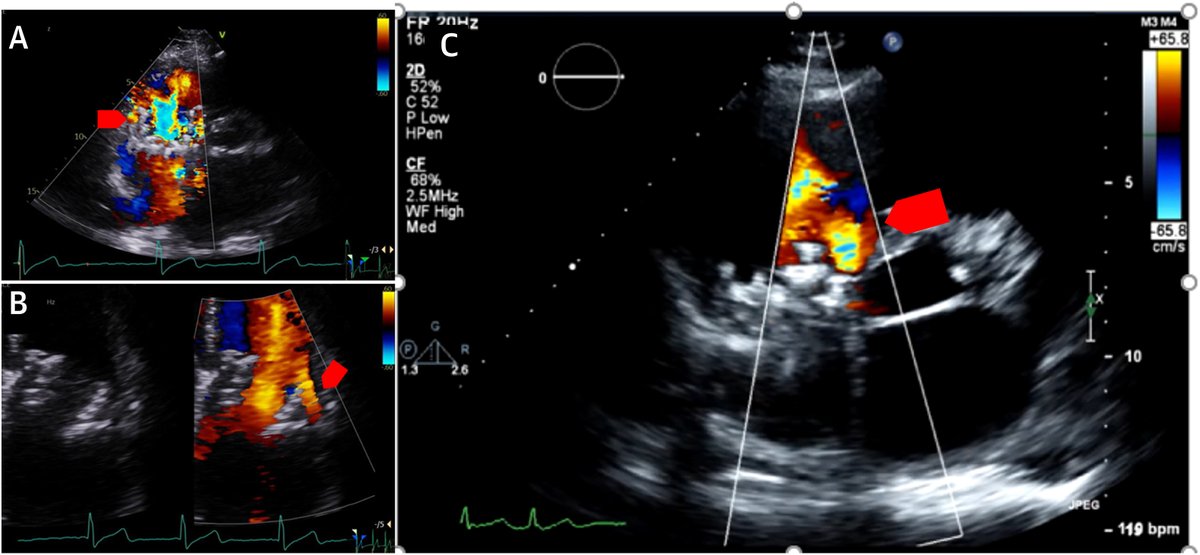

FANTASTIC MUST-READ #JACCIMG @JACCJournals SOTA review on Post #Evoque #TTVR Echo #TTE imaging. Comprehensive, practical! Download full paper here FREE for a LIMITED TIME! https://t.co/lfhJ0khJAw https://t.co/DgyCXnMOOF